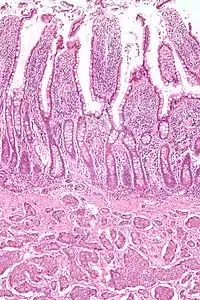

NETs are often small, yellow or tan masses, often located in the submucosa or more deeply intramurally, and they can be very firm due to an accompanying intense desmoplastic reaction. The overlying mucosa may be either intact or ulcerated. Some GEP-NETs invade deeply to involve the mesentery.[69] Histologically, NETs are an example of "small blue cell tumors," showing uniform cells which have a round to oval stippled nucleus and scant, pink granular cytoplasm. The cells may align variously in islands, glands or sheets. High power examination shows bland cytopathology. Electron microscopy can identify secretory granules. There is usually minimal pleomorphism but less commonly there can be anaplasia, mitotic activity, and necrosis.